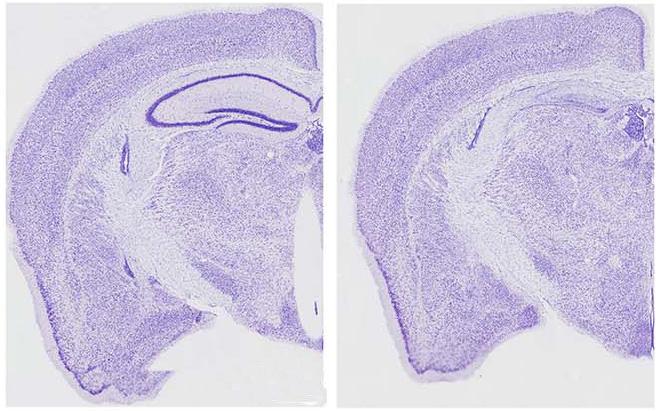

To do this, Dr. Ashe's group used fluorescent labeling to track and compare the behavior of normal and mutated tau in cultured neurons from the rat hippocampus, the brain region most associated with learning and memory. Unlike normal tau, both mutated tau and the short fragment produced when caspase-2 cuts tau were primarily found within structures called dendritic spines, where neurons receive inputs from neighboring cells. The overabundance of mutated tau, including the caspase-2-produced fragment, caused disruptions in synaptic function in the spines. The impact on synapses was specific, with no observed effects on the overall structure or survival of the neurons.